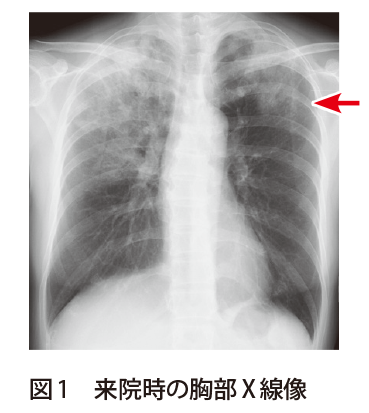

解答 解説 慢性咳嗽と発熱を主訴に受診した50歳代女性 実践 画像診断q A 羊土社 レジデントノート 羊土社

解答 解説 健診発見 無症状 胸部異常陰影で受診した30歳代男性 実践 画像診断q A 羊土社 レジデントノート 実践 画像診断q A 羊土社 レジデントノート 羊土社